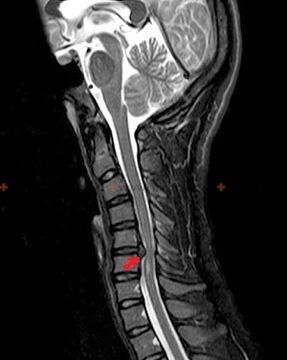

Diagnostic et signes radiologiques.

L'ostéochondrose est un diagnostic radiologique, car un tableau clinique détaillé n'est disponible qu'au moment de l'exacerbation, tandis que des modifications de la colonne vertébrale peuvent survenir avec le bien-être subjectif complet d'une personne. Sans examen radiologique, nous ne pouvons parler que d'une suspicion d'ostéochondrose, car des symptômes similaires peuvent être provoqués par d'autres maladies (myosite, néoplasmes vertébraux et autres).

Pour diagnostiquer l'ostéochondrose, les méthodes de recherche suivantes sont utilisées : radiographie (de préférence avec tests fonctionnels), MSCT et IRM. Cette dernière étude est préférable car elle permet de visualiser très clairement l'état des structures intervertébrales.

Les signes radiologiques de l'ostéochondrose comprennent les modifications suivantes dans la colonne vertébrale :

- Hauteur réduite des disques intervertébraux.

- Présence d’excroissances osseuses marginales.

- Violation de l'emplacement des vertèbres les unes par rapport aux autres.

- Déformations des corps vertébraux et des arcs vertébraux, etc.

La présence des changements décrits ci-dessus, ainsi que des changements dans la structure du disque intervertébral, détectés par MSCT et IRM, constituent des signes fiables confirmant la présence d'ostéochondrose.